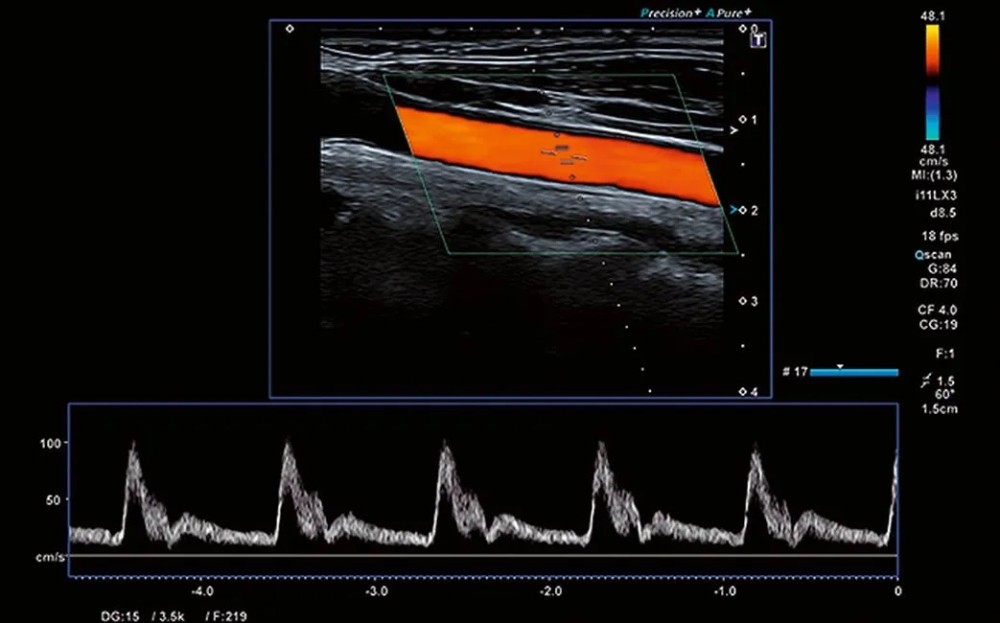

• Superb Microvascular Imaging (SMI)

Mikrodamar axınının aşağı sürətli hissələrinin kontrast maddəsi olmadan vizualizasiyası

Damar anomaliyalarının aşkarlanmasında kömək